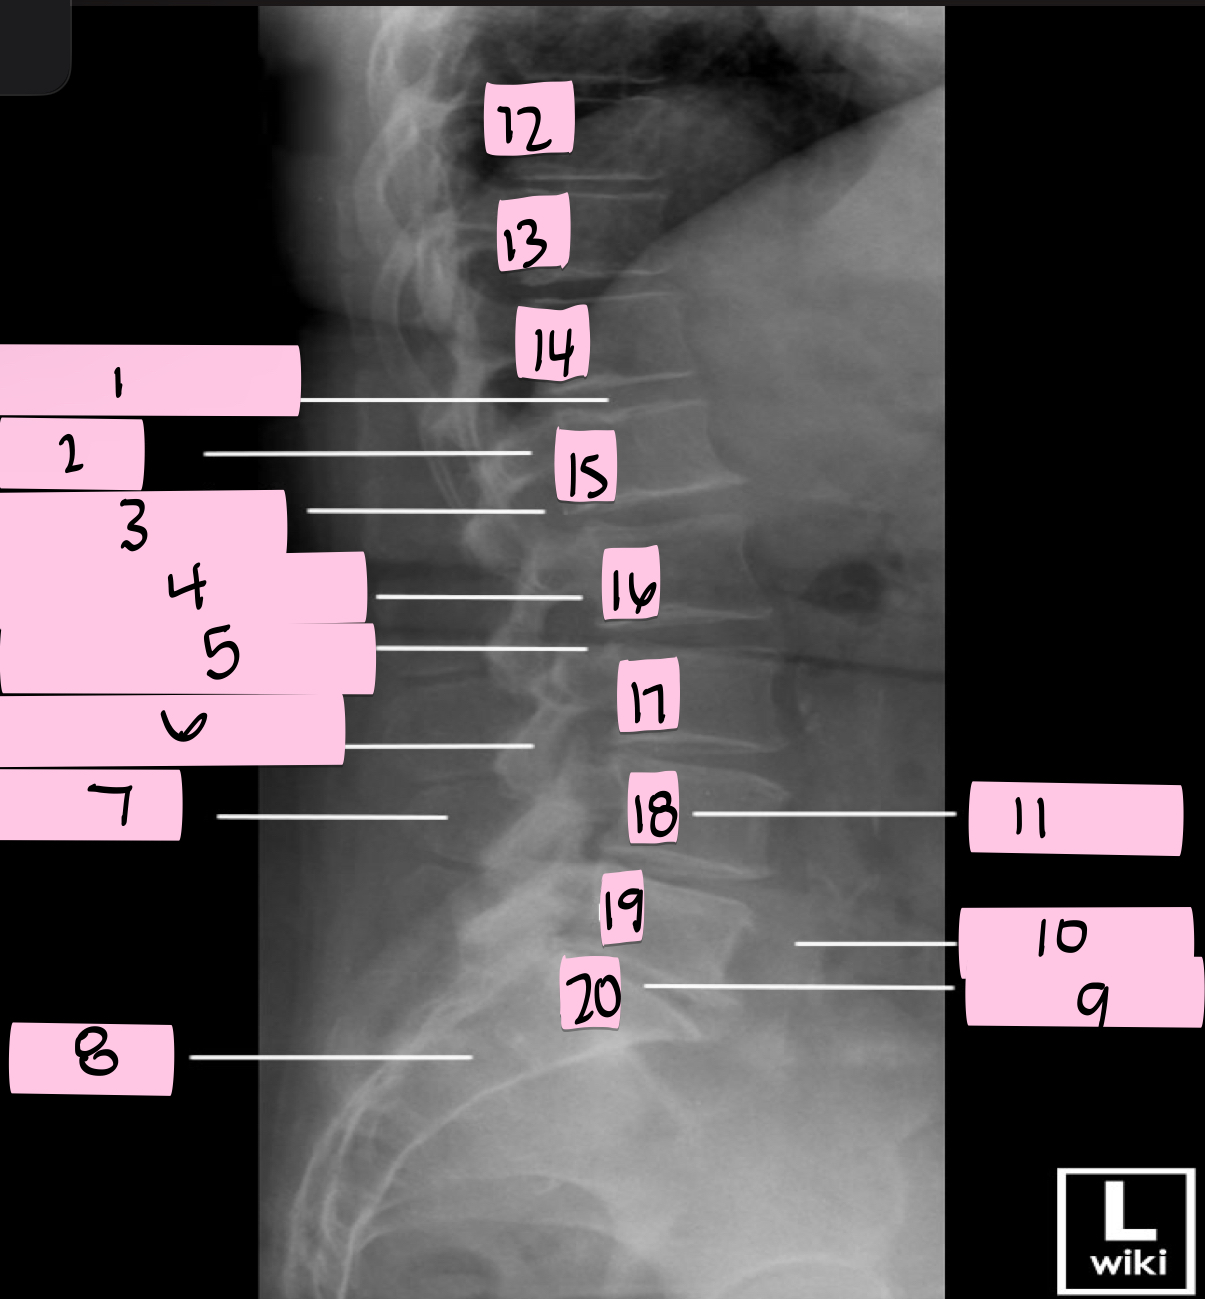

What is 1 pointing to?

Intervertebral disk

What is 2 pointing to?

Pedicle

What is 3 pointing to?

Intervertebral foramen

What is 4 pointing to?

Inferior vertebral notch

What is 5 pointing to?

Superior vertebral notch

What is 6 pointing to?

Inferior articular process

What is 7 pointing to?

Spinous process

What is 8 pointing to?

Sacrum

What is 9 pointing to?

L5 S1 joint

What is 10 pointing to?

Iliac crest

What is 11 pointing to?

Vertebral body (L4)

What is 12 pointing to?

T10

What is 13 pointing to?

T11

What is 14 pointing to?

T12

What is 15 pointing to?

L1

What is 16 pointing to?

L2

What is 17 pointing to?

L3

What is 18 pointing to?

L4

What is 19 pointing to?

L5

What is 20 pointing to?

S1